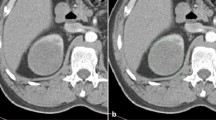

There was no significant difference in tumor sizes between the ccRCC and pRCC groups (p = 0.94). The CTTA parameters for ccRCC and pRCC and their value in differentiating the two entities are given in Table 2. The box and whisker plot of entropy values of renal cancers at medium spatial filter is given in Fig. 3. Entropy with fine and medium spatial filters of ccRCC was significantly higher than that of pRCC (p = 0.047 and 0.033, respectively).

Box and whisker plot of entropy values for papillary (pRCC) and clear cell (ccRCC) renal cancers at medium spatial scaling filter (SSF = 4). Pap RCC, papillary-type renal cell carcinoma; ccRCC, clear cell–type renal cell carcinoma. Boxes represent interquartile range. Central line in the box is the median value. Whiskers represent range of all values. Small circles and triangles refer to outliers. Note that the boxes of the two groups of RCC do not overlap